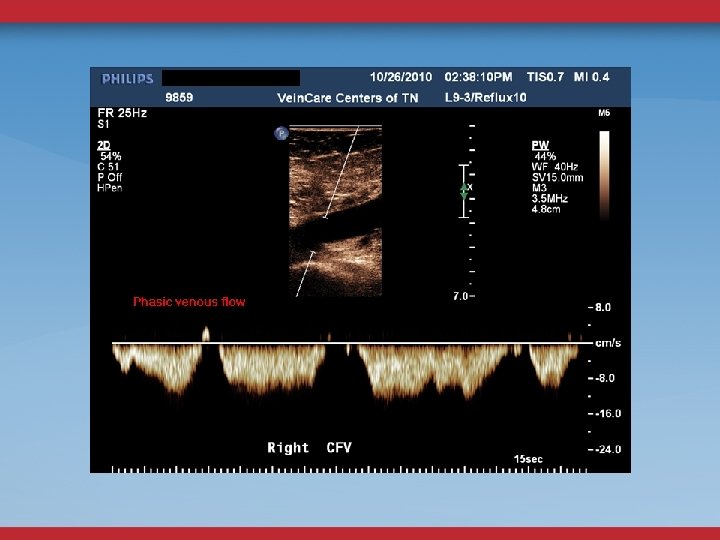

LE VENOUS DUPLEX US REFLUX OBSTRUCTION CFV DOPPLER FLOW CONTINUOUS? ASYMMETRY? FEMORAL VEIN COLLATERALS

ABDOMINAL/PELVIC DUPLEX FLOW AND ANATOMY STENOSIS MINOR DIAMETER REDUCTION ELEVATED PEAK VENOUS VELOCITY RATIO >2. 5 FLOW REVERSAL GONADAL, ASCENDING LUMBAR, PELVIC VARICOSITIES